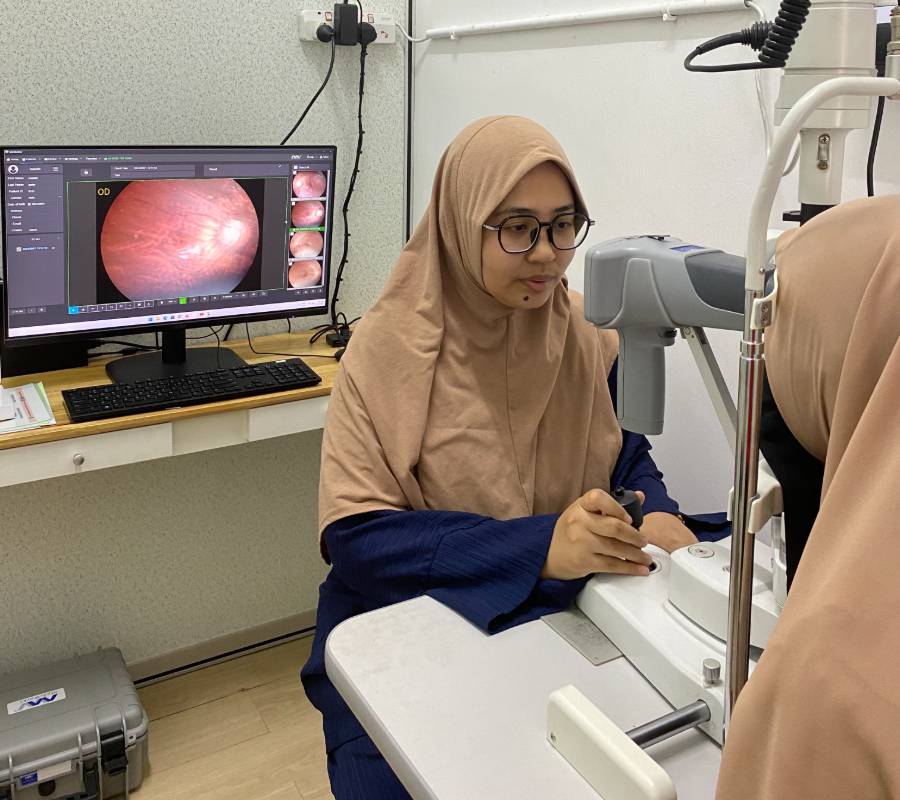

Pakar Optometri Berpengalaman

Pemeriksaan menyeluruh ke atas bahagian hadapan (anterior) dan belakang (posterior) mata—termasuk kornea, kanta, iris, retina serta saraf optik.